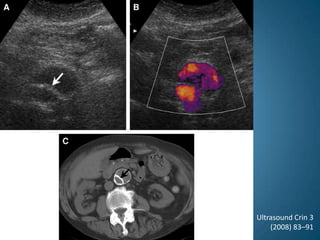

Placa de ateroma y aneurisma en USGUltrasound Crin 3 (2008)83–91

Placa de ateromay aneurisma en USGUltrasound Crin 3 (2008)83–91

Ultrasonido abdominalEs el método de elección en un paciente con sospechaTiene una sensibilidad de casi el 100%, permite realizar mediciones en plano longitudinal y transverso, con una variabilidad de 0.6 cmNo es invasivo, no requiere medio de contraste, es accesible, seguroEs un estudio operador – dependienteDa información insuficiente para plantear la cirugía de reconstrucciónUltrasound Crin 3 (2008)83–91

Ultrasonido abdominalEs impreciso en determinar límites, así como en detectar mas del 50% de los casos, una vez que hay rupturaDa información  insuficiente sobre la vasculatura visceralDa información imprecisa en obesos, o con abdomen distendido por gas intestinal (2-3% de los casos)Es de elección como herramienta diagnóstica inicial y para seguimiento, en pacientes en los que no está indicada cirugía, en el momento del diagnósticoUltrasound Crin 3 (2008)83–91

Ultrasonido abdominalEs elmétodo de elección en un paciente con sospechaTiene una sensibilidad de casi el 100%, permite realizar mediciones en plano longitudinal y transverso, con una variabilidad de 0.6 cmNo es invasivo, no requiere medio de contraste, es accesible, seguroEs un estudio operador – dependienteDa información insuficiente para plantear la cirugía de reconstrucciónUltrasound Crin 3 (2008)83–91

Ultrasonido abdominalEs imprecisoen determinar límites, así como en detectar mas del 50% de los casos, una vez que hay rupturaDa información  insuficiente sobre la vasculatura visceralDa información imprecisa en obesos, o con abdomen distendido por gas intestinal (2-3% de los casos)Es de elección como herramienta diagnóstica inicial y para seguimiento, en pacientes en los que no está indicada cirugía, en el momento del diagnósticoUltrasound Crin 3 (2008)83–91